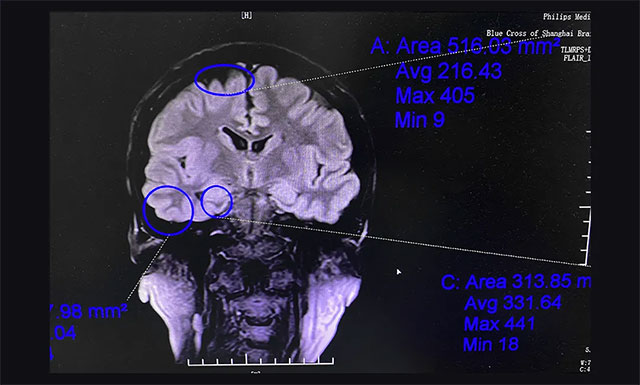

▲ 通过系列检查评估,最终明确患者致癫灶

杨忠旭教授团队通过美国尼高力视频脑电监测、核磁共振等评估,最终明确患者致癫灶为双侧起源,右侧大脑为主要异常放电起源。手术指征明确,未见明显手术禁忌症。